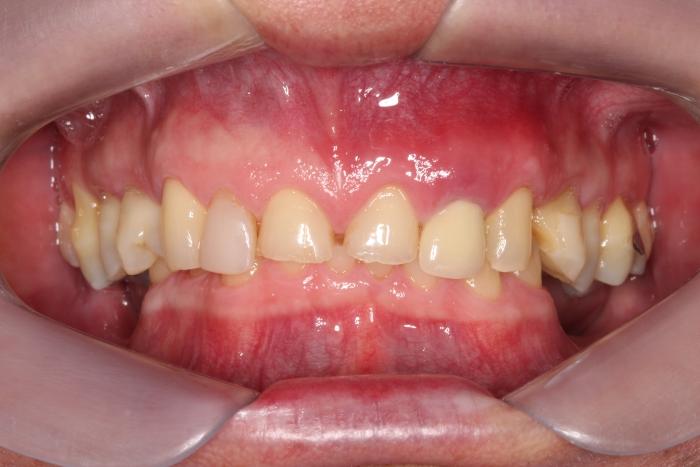

Imagem inicial em 2014

Sorriso inicial, em 2014